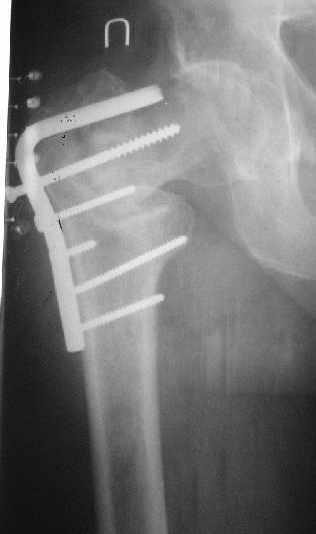

Как предлагали уважаемые коллеги, сегодня наложили спице-стержневой дистрактор таз-бедро, перед этим попробовали закрытую остеоклазию под в/в анестезией, движение в т/б суставе ( или в ложном суставе! ) восстановлен.

Р-снимки сразу п/о, следующий после дистракции, аксиальная - прощу извинения за плохое качество снимков.

Мне кажется надо еще продолжать постепенную дистракцию. И еще которая наверху шейки по моему это осколок от шейки, и она фиксирована оссификатом надвертлужной обл. Поэтому при повторной операции видимо придется открыто мобилизовать т/б сустав.

С уважением Абдурашид.